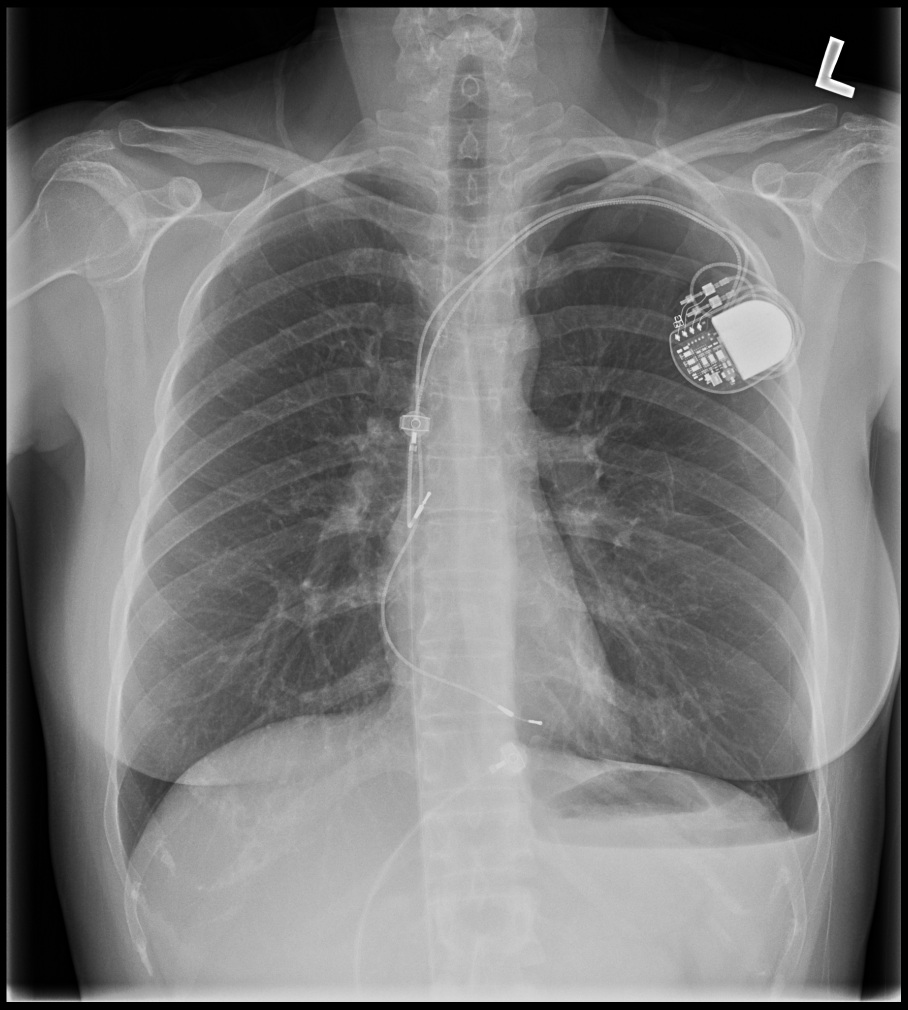

Post procedure CXR

pneumothorax_post_ppm.jpg